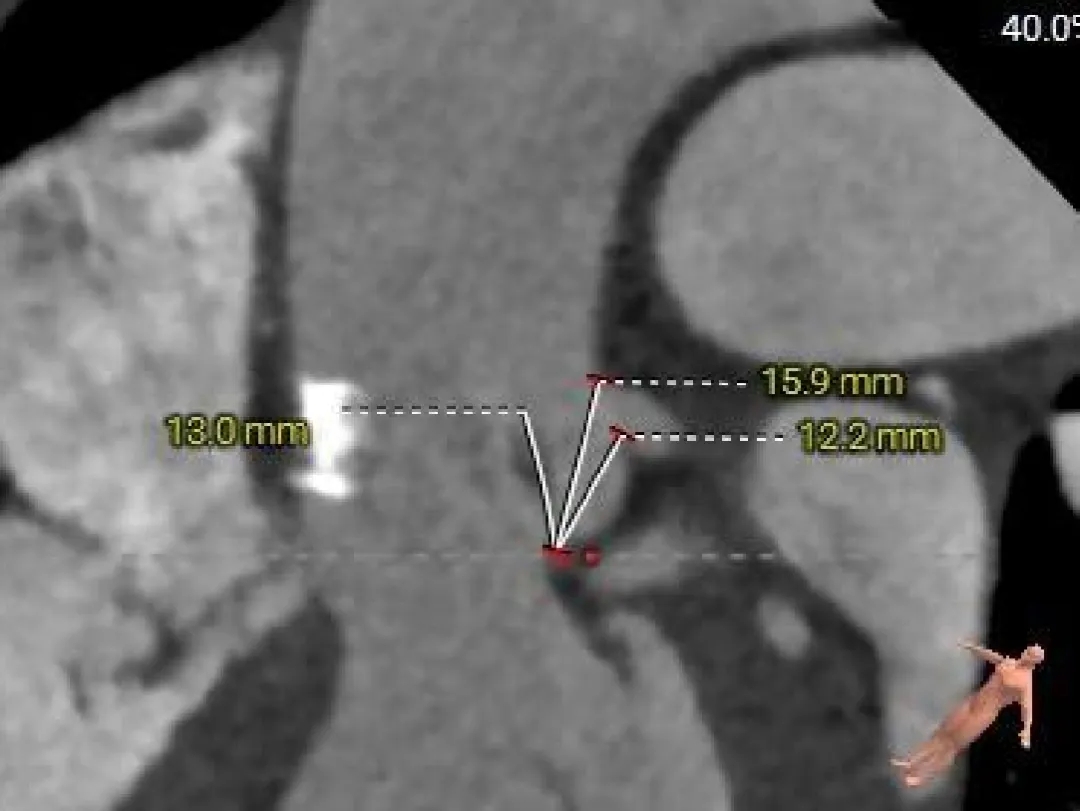

主动脉根部测量

Left Coronary

11.5mm

LCA & Leaflet

12.2mm<13.0mm

Right Coronary

10.5mm

RCA & Leaflet

13.3mm<13.5mm

-

左、右冠脉高度偏低

双侧瓣叶偏长

结合SOV、STJ内径评估冠脉风险适中,结合球扩情况充分评估